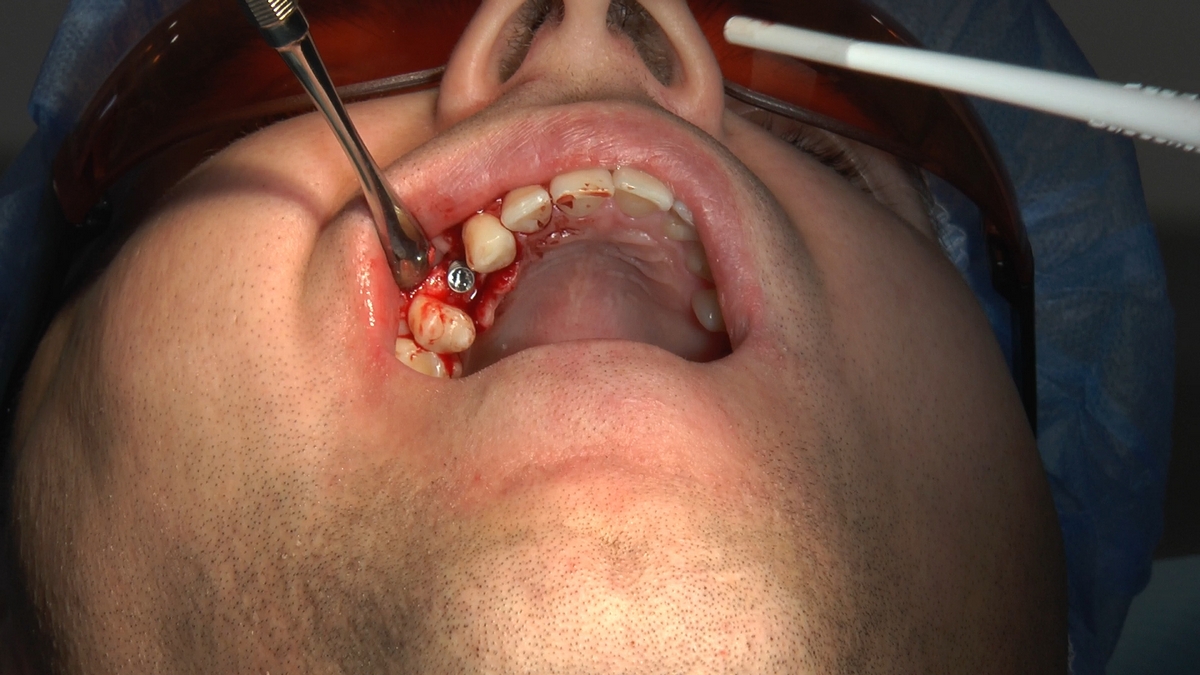

W trakcje dwóch dni zabiegowych, piątek i sobota, 5 i 6 października 2018 roku, lekarze uczestniczący w 6 Sesji VI Sezonu, wykonali wiele zabiegów o wysokim stopniu trudności. Przeprowadzili je pod kierunkiem Mentorów Instytutu Vivadental – dr n.med. Violetty Szycik, dr n.med. Magdaleny Kisłowskiej-Syryczyńskiej oraz dr Małgorzaty Piotrowskiej.

Wprowadziliśmy łącznie 25 implantów w tym wykonaliśmy:

dwa zabiegi All- on -4 / jeden w szczęce, jeden w żuchwie/ z usunięciem zębów i natychmiastową implantacją oraz natychmiastową odbudową protetyczną